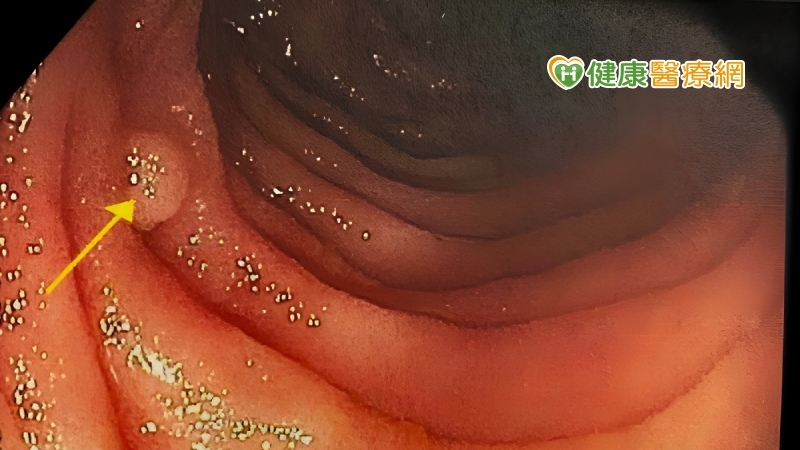

在大腸直腸癌出現前的亞健康階段,也就是已有疾病發生,但尚無症狀,這個階段可透過糞便潛血檢查或大腸鏡檢查進行次段預防,檢測是否有腺腫或早期癌症。